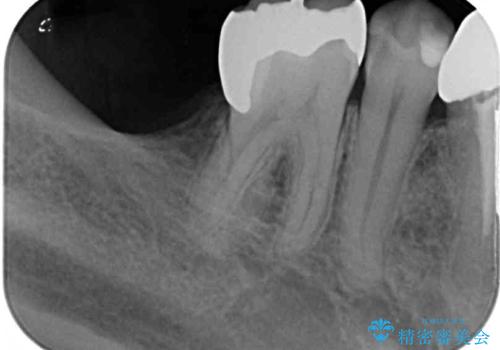

- 下顎左右の奥歯を治療途中で放置してしまっているとのことで来院された患者様です。

欠損部はインプラントによる補綴治療を、土台の外れてしまった歯は、根管治療を行った上で、補綴治療を行うこととしました。